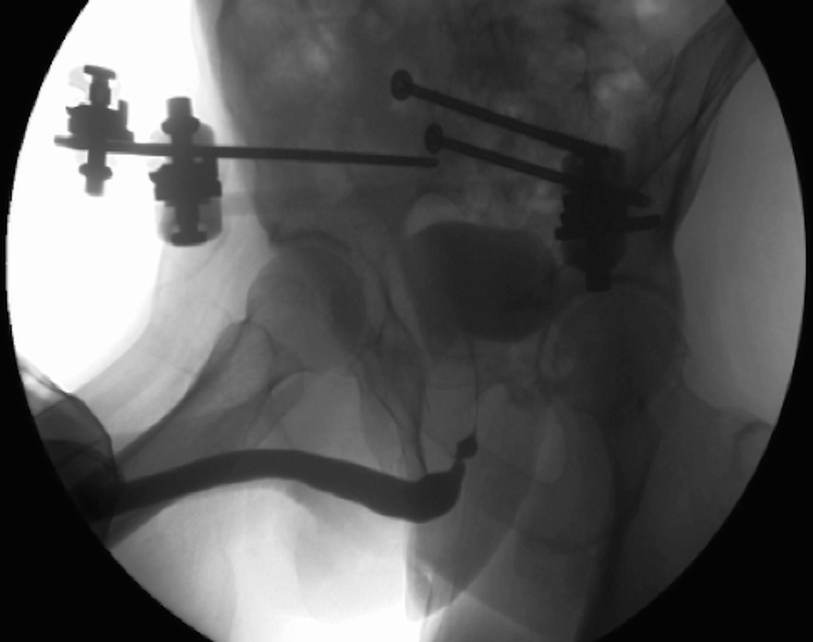

5.3.2 Retrograde Urethrogram and Voiding Cystourethrogram

A retrograde urethrogram demonstrating a non-obliterated urethral stenosis associated with a pelvic fracture injury